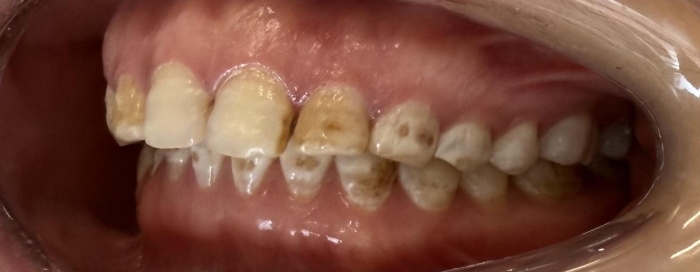

党秀医生接诊,为她进行了全面的口腔检查和美学评估。患者牙齿牙面呈深黄色斑块状,唇侧釉质多处片状缺损,边缘粗糙,部分区域浅层牙本质暴露,进冷热食物时常有不适。其余牙齿也存在不同程度的色素沉着,整体颜色晦暗。结合病史及临床检查,诊断为重度氟斑牙伴牙釉质缺损。

针对患者“既要恢复功能,又要美观自然”的诉求,党秀定制了“全口牙齿美白+美学修复”的诊疗方案。首先,对全口牙齿进行渗透树脂美白,将基础牙齿色调提亮2-3个色阶,使其他牙齿与后续贴面修复后的上前牙颜色协调;其次,开展上前牙贴面美学修复,制作超薄瓷贴面,恢复牙体外形、遮色并重建缺损的釉质层。全程治疗周期约10天,患者无明显不适。